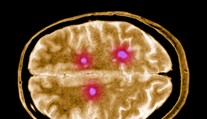

Vedci odhalili bunky, ktoré ničia mozog. Objav môže zmeniť liečbu sklerózy Gabriela Šlebodová 18. 10. 2025